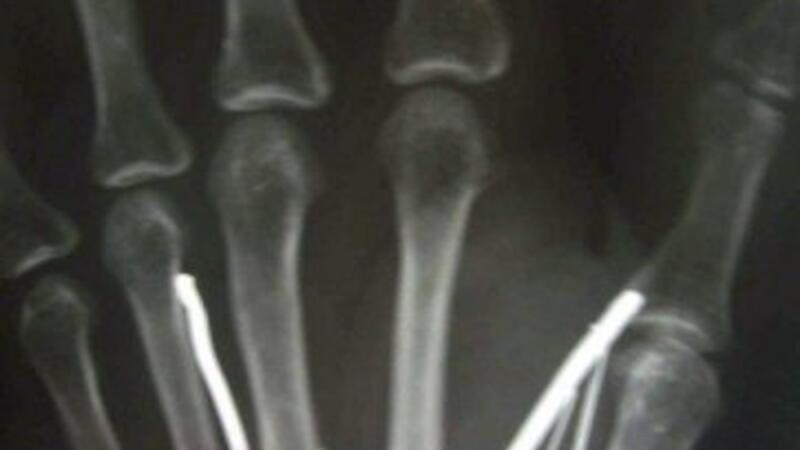

ونجح الجراحون في مستشفى كامبوروبيتيا (جنوب سريلانكا) في انتزاع 19 مسمارا معدنيا من أصل 24 يصل طول بعضها إلى خمسة سنتيمترات بالإضافة إلى إبرة غرست في ذراعيها ورجليها وجبينها. أتى ذلك خلال عملية جراحية استمرت ثلاث ساعات.

ونقل غاجاديرا عنها أن "مخدومها أحمى المسامير المعدنية ومن ثم أدخلها في جسدها مستخدما المطرقة. أضاف أنهم وجدوا "المسامير في ذراعيها ورجليها وجبينها".

وكانت أرياواتي قد أدخلت إلى المستشفى في نهاية الأسبوع الماضي بعدما عادت إلى الديار وهي تشكو من آلام مبرحة، وقد عجزت عن السير. وتمكن الجراحون من انتزاع 13 مسمارا كبيرا كل واحد منها يبلغ خمسة سنتيمرات، بالإضافة إلى ستة مسامير صغيرة بحسب غاجاديرا. وأوضح أنه لم يتم نزع المسامير المتبقية لأنه كان من الممكن أن يتسبب ذلك بضرر في الأعصاب.